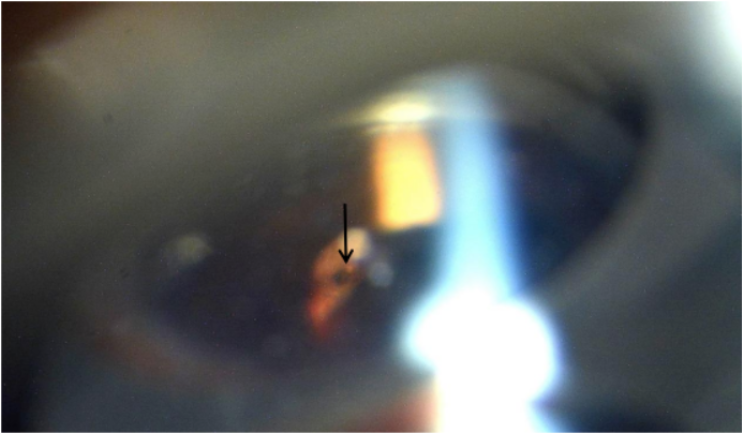

进一步三面镜下检查可见下方5点锯齿缘附近长条形棕色异物改变、铁锈色包裹。

三面镜检查位于5点处铁锈色改变异物残存